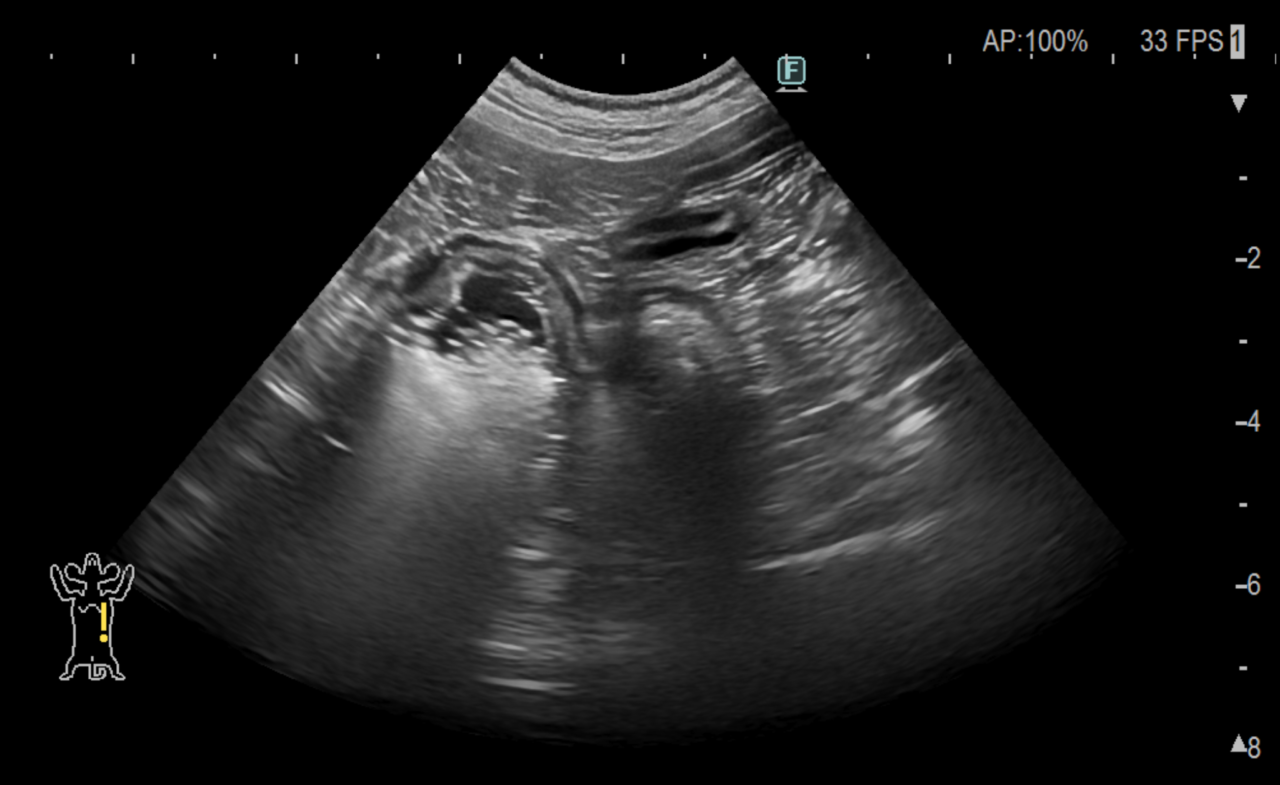

腹部エコー検査、CT検査で胃の幽門部に異物が確認されたため内視鏡による摘出を試みました。